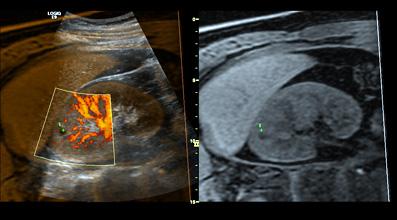

The LOGIQ E9 includes volume navigation, a tool incorporating two key components to maximize the system’s ultrasound architecture: fusion to combine the advantages of real-time ultrasound imaging with the high spatial and contrast resolution of CT, MR or PET; and a GPS-like technology to track and mark a patient’s anatomy during the ultrasound exam.

GE said the LOGIQ E9 helps address the biggest challenge in ultrasound radiology and vascular care – how to leverage clinical images from previous diagnostic imaging studies for interventional or diagnostic ultrasound procedures.